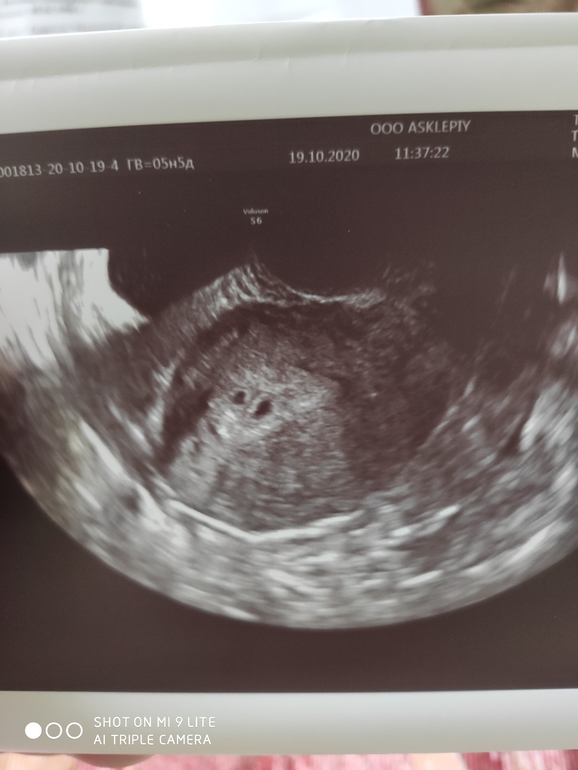

Двойня малого срока.

У меня был срок 6,3 Малыши на 5/6 недель. По ктр они на 5 тянут

А у вас уже подтвердили двойню по узи на таком сроке?

Да подтвердили